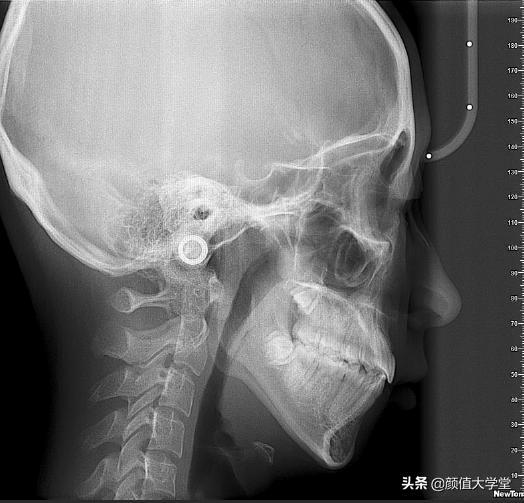

3、下颌骨发育不良

如果是下颌骨发育不良导致的下巴后缩,除了通过医美手段来改善,否则基本就要一辈子做个下巴后缩的人了,毕竟这种情况属于最根本的骨性原因。

下巴截骨前移手术做成功就能管一辈子,也不用担心像假体丰下巴有可能面临的感染、排异情况的发生。下巴截骨前移手术分为了两种,像一般中重度下巴后缩的人都可以采用水平截骨前移的手术方法,具体如下:

而双阶梯截骨前移手术适合下巴后缩的特别严重的人群,就因为下巴后缩的太严重所以前移一块儿不能解决问题,需要前移两块儿,所以才会叫“双阶梯”。

像这两种手术前移调节好位置以后都会用钛钉钛板固定,现在有可溶性钛钉,一般8~12个月之后就会被溶解吸收掉。就算是以前的钛板钛钉不能溶解掉,如果不喜欢体内有异物,也可以等骨骼痊愈之后去医院取出来的。